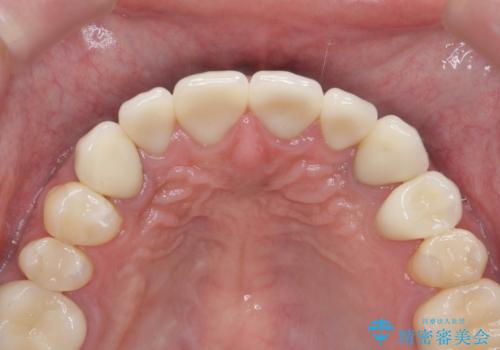

複数箇所コンポジット充填された前歯をセラミック治療

充填部位が大きく、再度充填をするには神経と近くなり抜髄のリスクが高まるため、劣化の少ないセラミックでフルカバーするセラミッククラウン治療を行うこととしました。

- 79.2万円(ジルコニアクラウン×6・仮歯×6)費用は治療当時の料金となります

しかし、経年劣化が早く着色や小さな虫歯が再発しやすいため、ある程度の大きさになってしまった場合セラミッククラウンで置き替えた方が神経を温存し長期的な予後の期待できる治療となります。